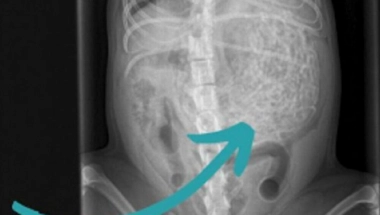

Veterinarski pregled pokazao je da pas ima nešto neobično u stomaku, pa su se odmah odlučili za operaciju. Izvađeno mu je oko 60 gumica teških 200 grama, a pas Hem ima samo šest kilograma.

Na ultrazvuku je otkriveno da je pas pojeo 200 grama gumica za kosu!